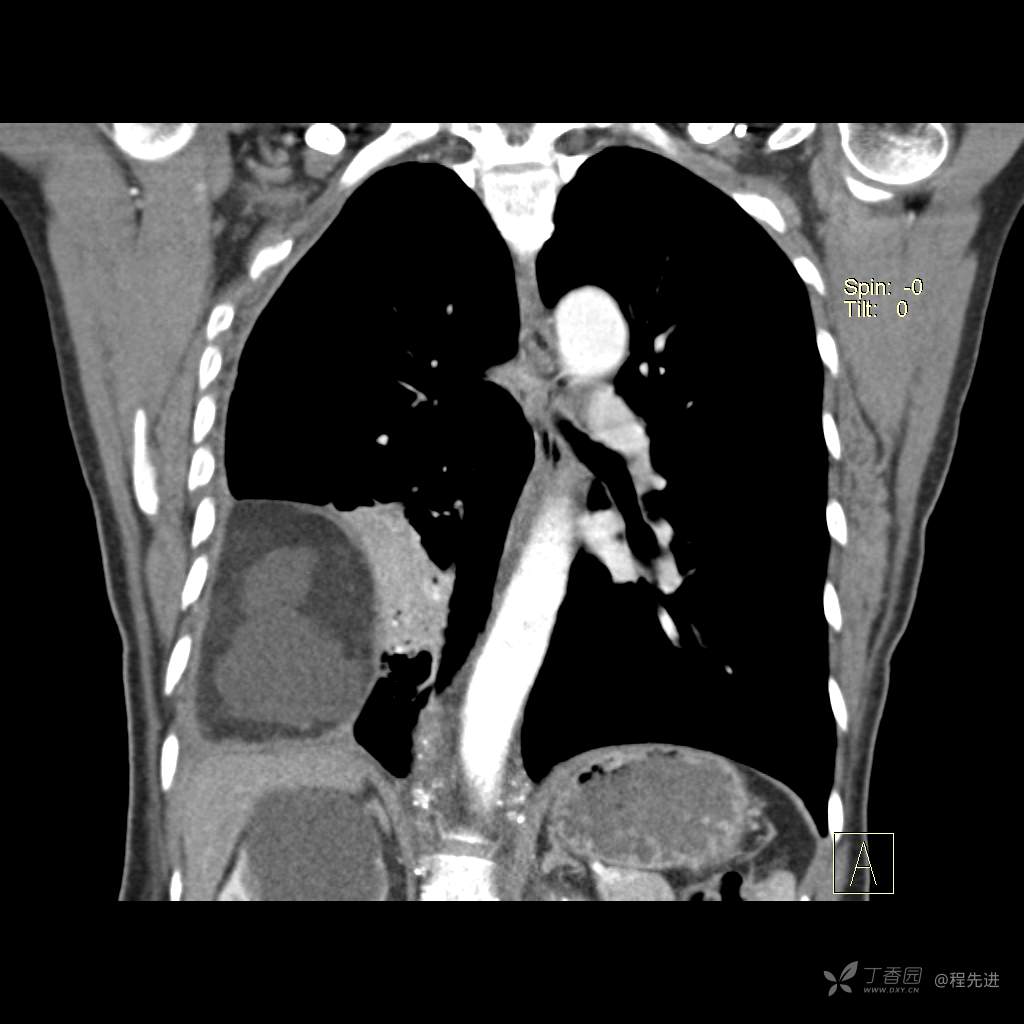

患者性别:女

患者年龄:51岁

简要病史:胸闷半年

肺淋巴管肌瘤病 (7)

乳糜胸 (8)